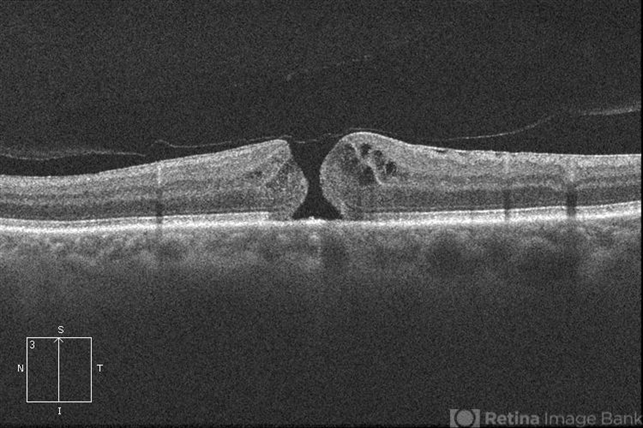

- macular hole

Cirrus